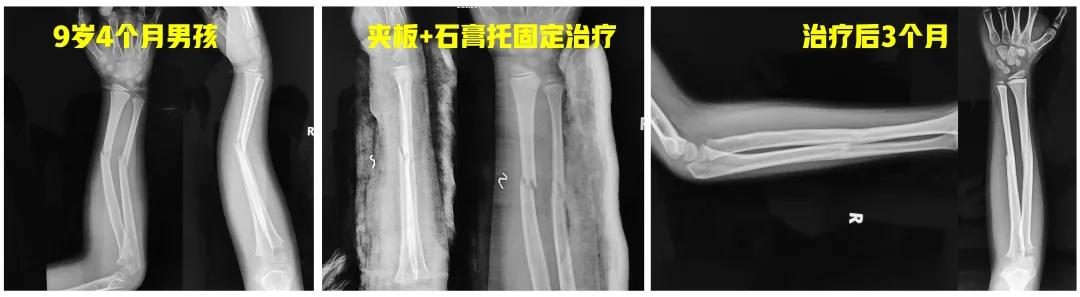

老师: 下面两个病例,分别是9岁4个月男孩的前臂中段骨折,保守治疗后3个月骨折对位、愈合良好。另外一个12岁男孩,早期外院保守治疗,三周时骨折再移位,于我院再次整复后恢复满意。

前臂远端骨折相对表浅,肌肉附着也少,外固定相对容易维持,临床用中医传统前臂夹板或者西医推荐的塑形良好的前臂石膏管型,都比较容易维持住骨折对位。而前臂近1/3骨折,附于骨折近端的肱二头肌与旋后肌均为跨肘关节肌肉,一般的前臂夹板就不能很好维持放松肌肉的屈肘、前臂旋后的位置,所以就不太适合。